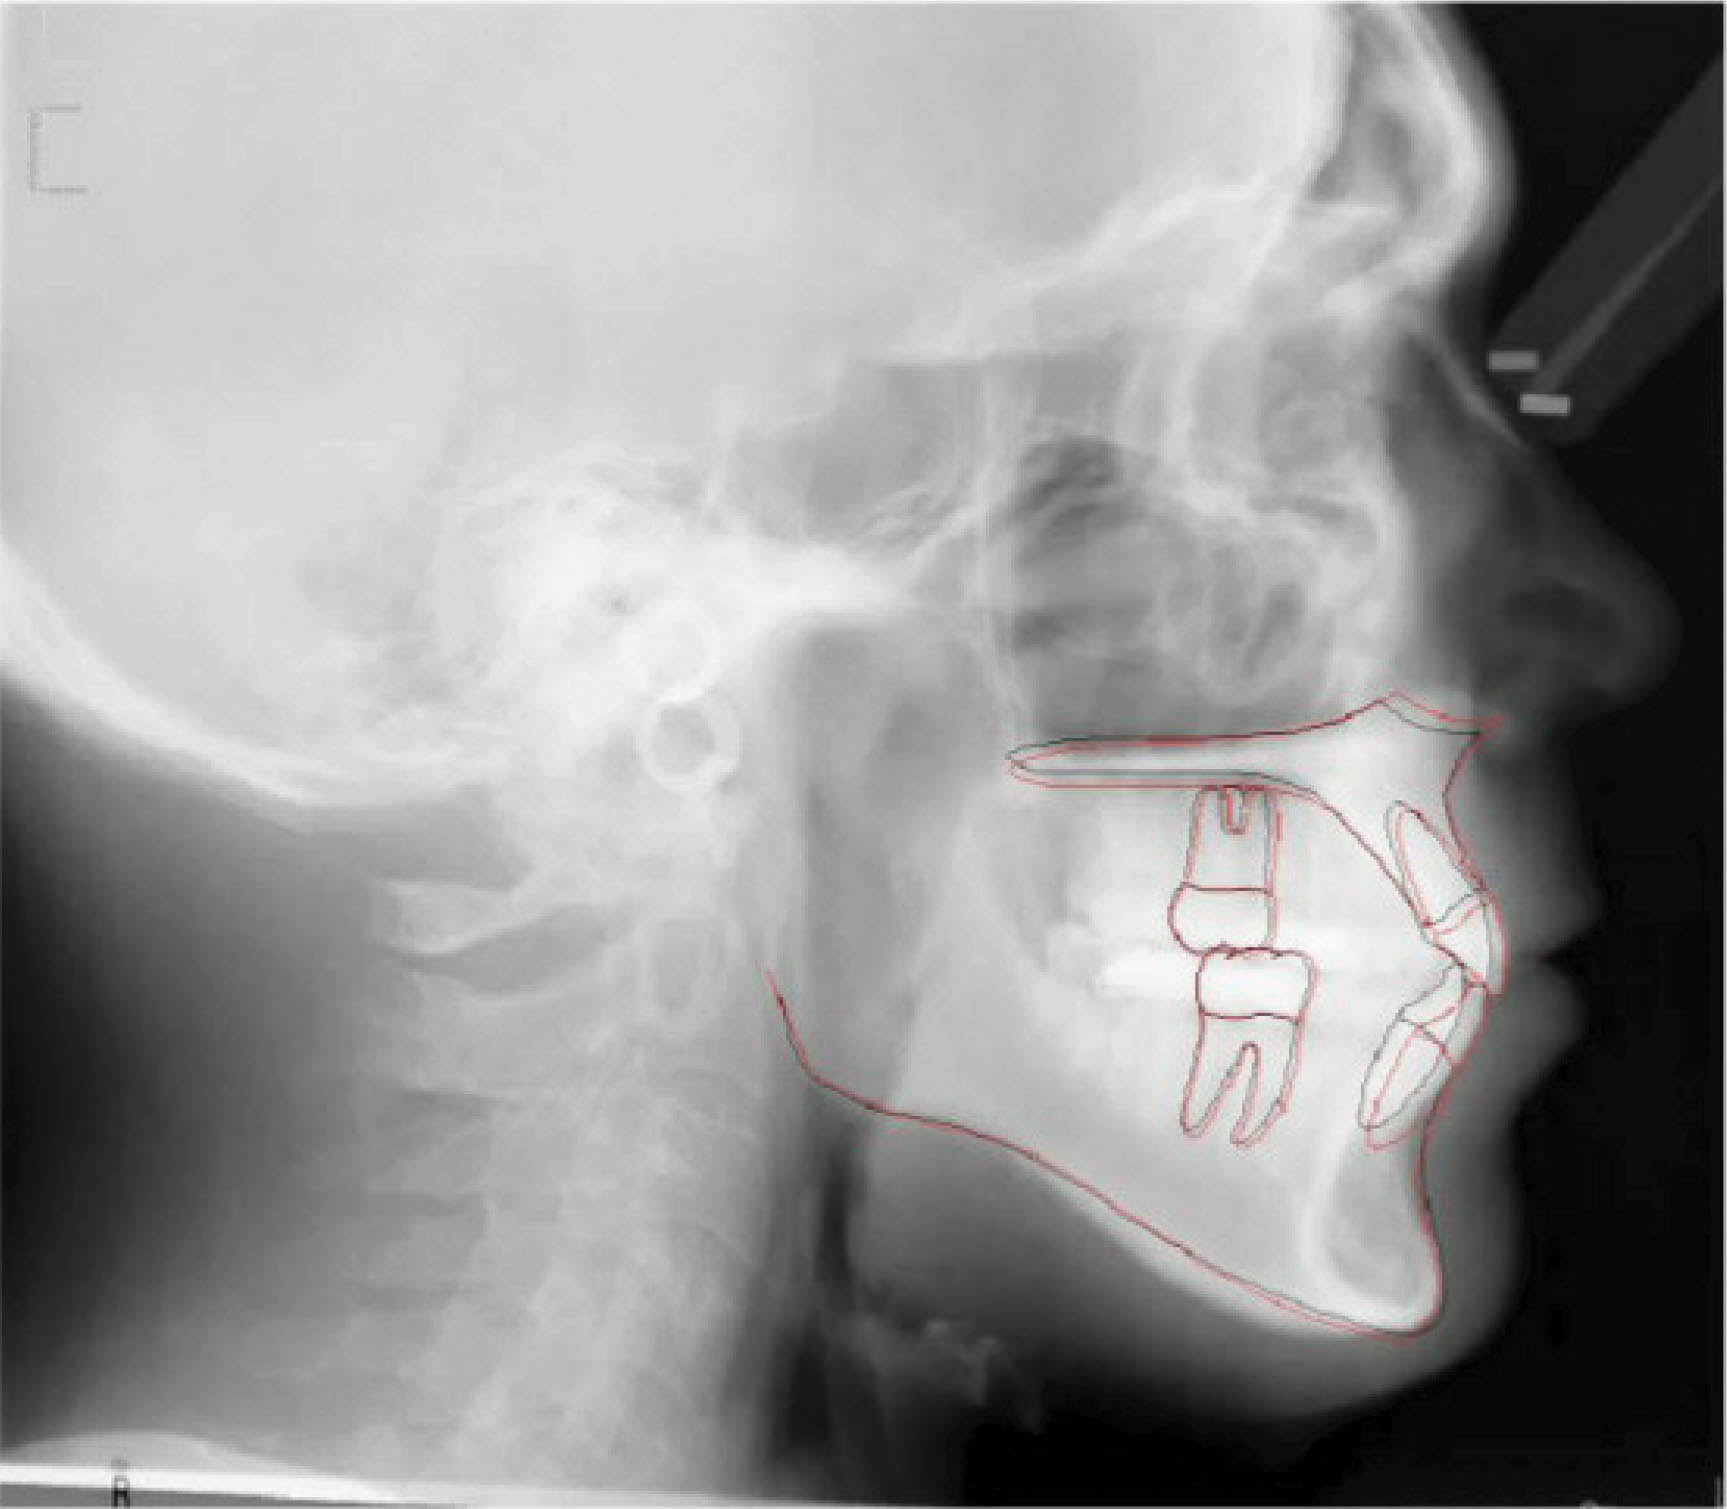

شکل 15-6

شکل 16-6

شکل 17-6

بیمار بعدی یک بیمارکلاسI با میزان متوسطی از کرادینگ در هر دو فک است. به کانینهایی که شدیداً چرخیدهاند دقت کنید (شکل 15-6 تا 17-6). این بیماران به ارتودنسی شفاف عالی جواب میدهند. یک دختر دبیرستانی که نمیخواهد در جشن فارغ التحصیلی خود و عکسهایی که در کلاس میگیرد براکت داشته باشد، خیلی خوب از الاینرهای شفاف استفاده میکند.